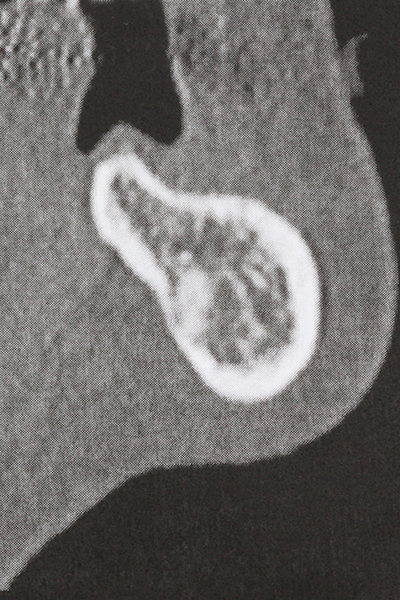

Die Präparation des lateralen Fensters bei der externen Sinusbodenelevation stellt gerade für chirurgisch unerfahrene Implantologen eine große Herausforderung dar. Die knöcherne Bedeckung der Kieferhöhle ohne eine Verletzung der darunterliegenden Schneider’schen Membran abzutragen ist dabei nur ein Teil der Operation – nach Schaffung eines ausreichenden Zugangs muss die Kieferhöhlenschleimhaut vorsichtig mobilisiert werden, um Raum für das einzubringende Material bzw. die Implantate zu schaffen. In dieser Indikation ist die Piezochirurgie zweierlei hilfreich: zum einen kann durch Verwendung diamantierter Instrumente eine selektive Knochenabtragung erfolgen und die darunter liegende Schleimhaut bleibt bei vorsichtiger Vorgehensweise intakt. Zum anderen unterstützen die Ultraschallfrequenzen zusätzlich eine komplikationslose Ablösung der Schleimhaut – sie werden durch spezielle stumpfe Ansätze in den Spaltraum zwischen Schleimhaut und Kieferhöhlenboden übertragen (Cassetta, Ricci et al. 2012, Pereira, Gealh et al. 2014) (Rickert, Vissink et al. 2013). So erscheint es nicht verwunderlich, dass in aktuellen Übersichtsarbeiten über die externe Sinusbodenelevation neben der Verwendung von rauen Implantatoberflächen und dem Einsatz von Knochenersatzmaterialien auch der Einsatz von piezoelektronischen Geräten als positiv bewertet wird (Wallace, Tarnow et al. 2012).

Weitere Einsatzgebiete ergeben sich in der Kieferhöhlenchirurgie: Hier können nach konzentrischer Präparation eines in der Regel trapezförmigen Knochendeckels der fazialen Kieferhöhlenwand Pathologien und Fremdkörper aus der Kieferhöhle entfernt werden. Der Knochendeckel wird nach Abschluss des intra-antralen Operationsanteils reponiert und durch Verkeilen oder adaptierende Nähte gegen Dislokation gesichert.